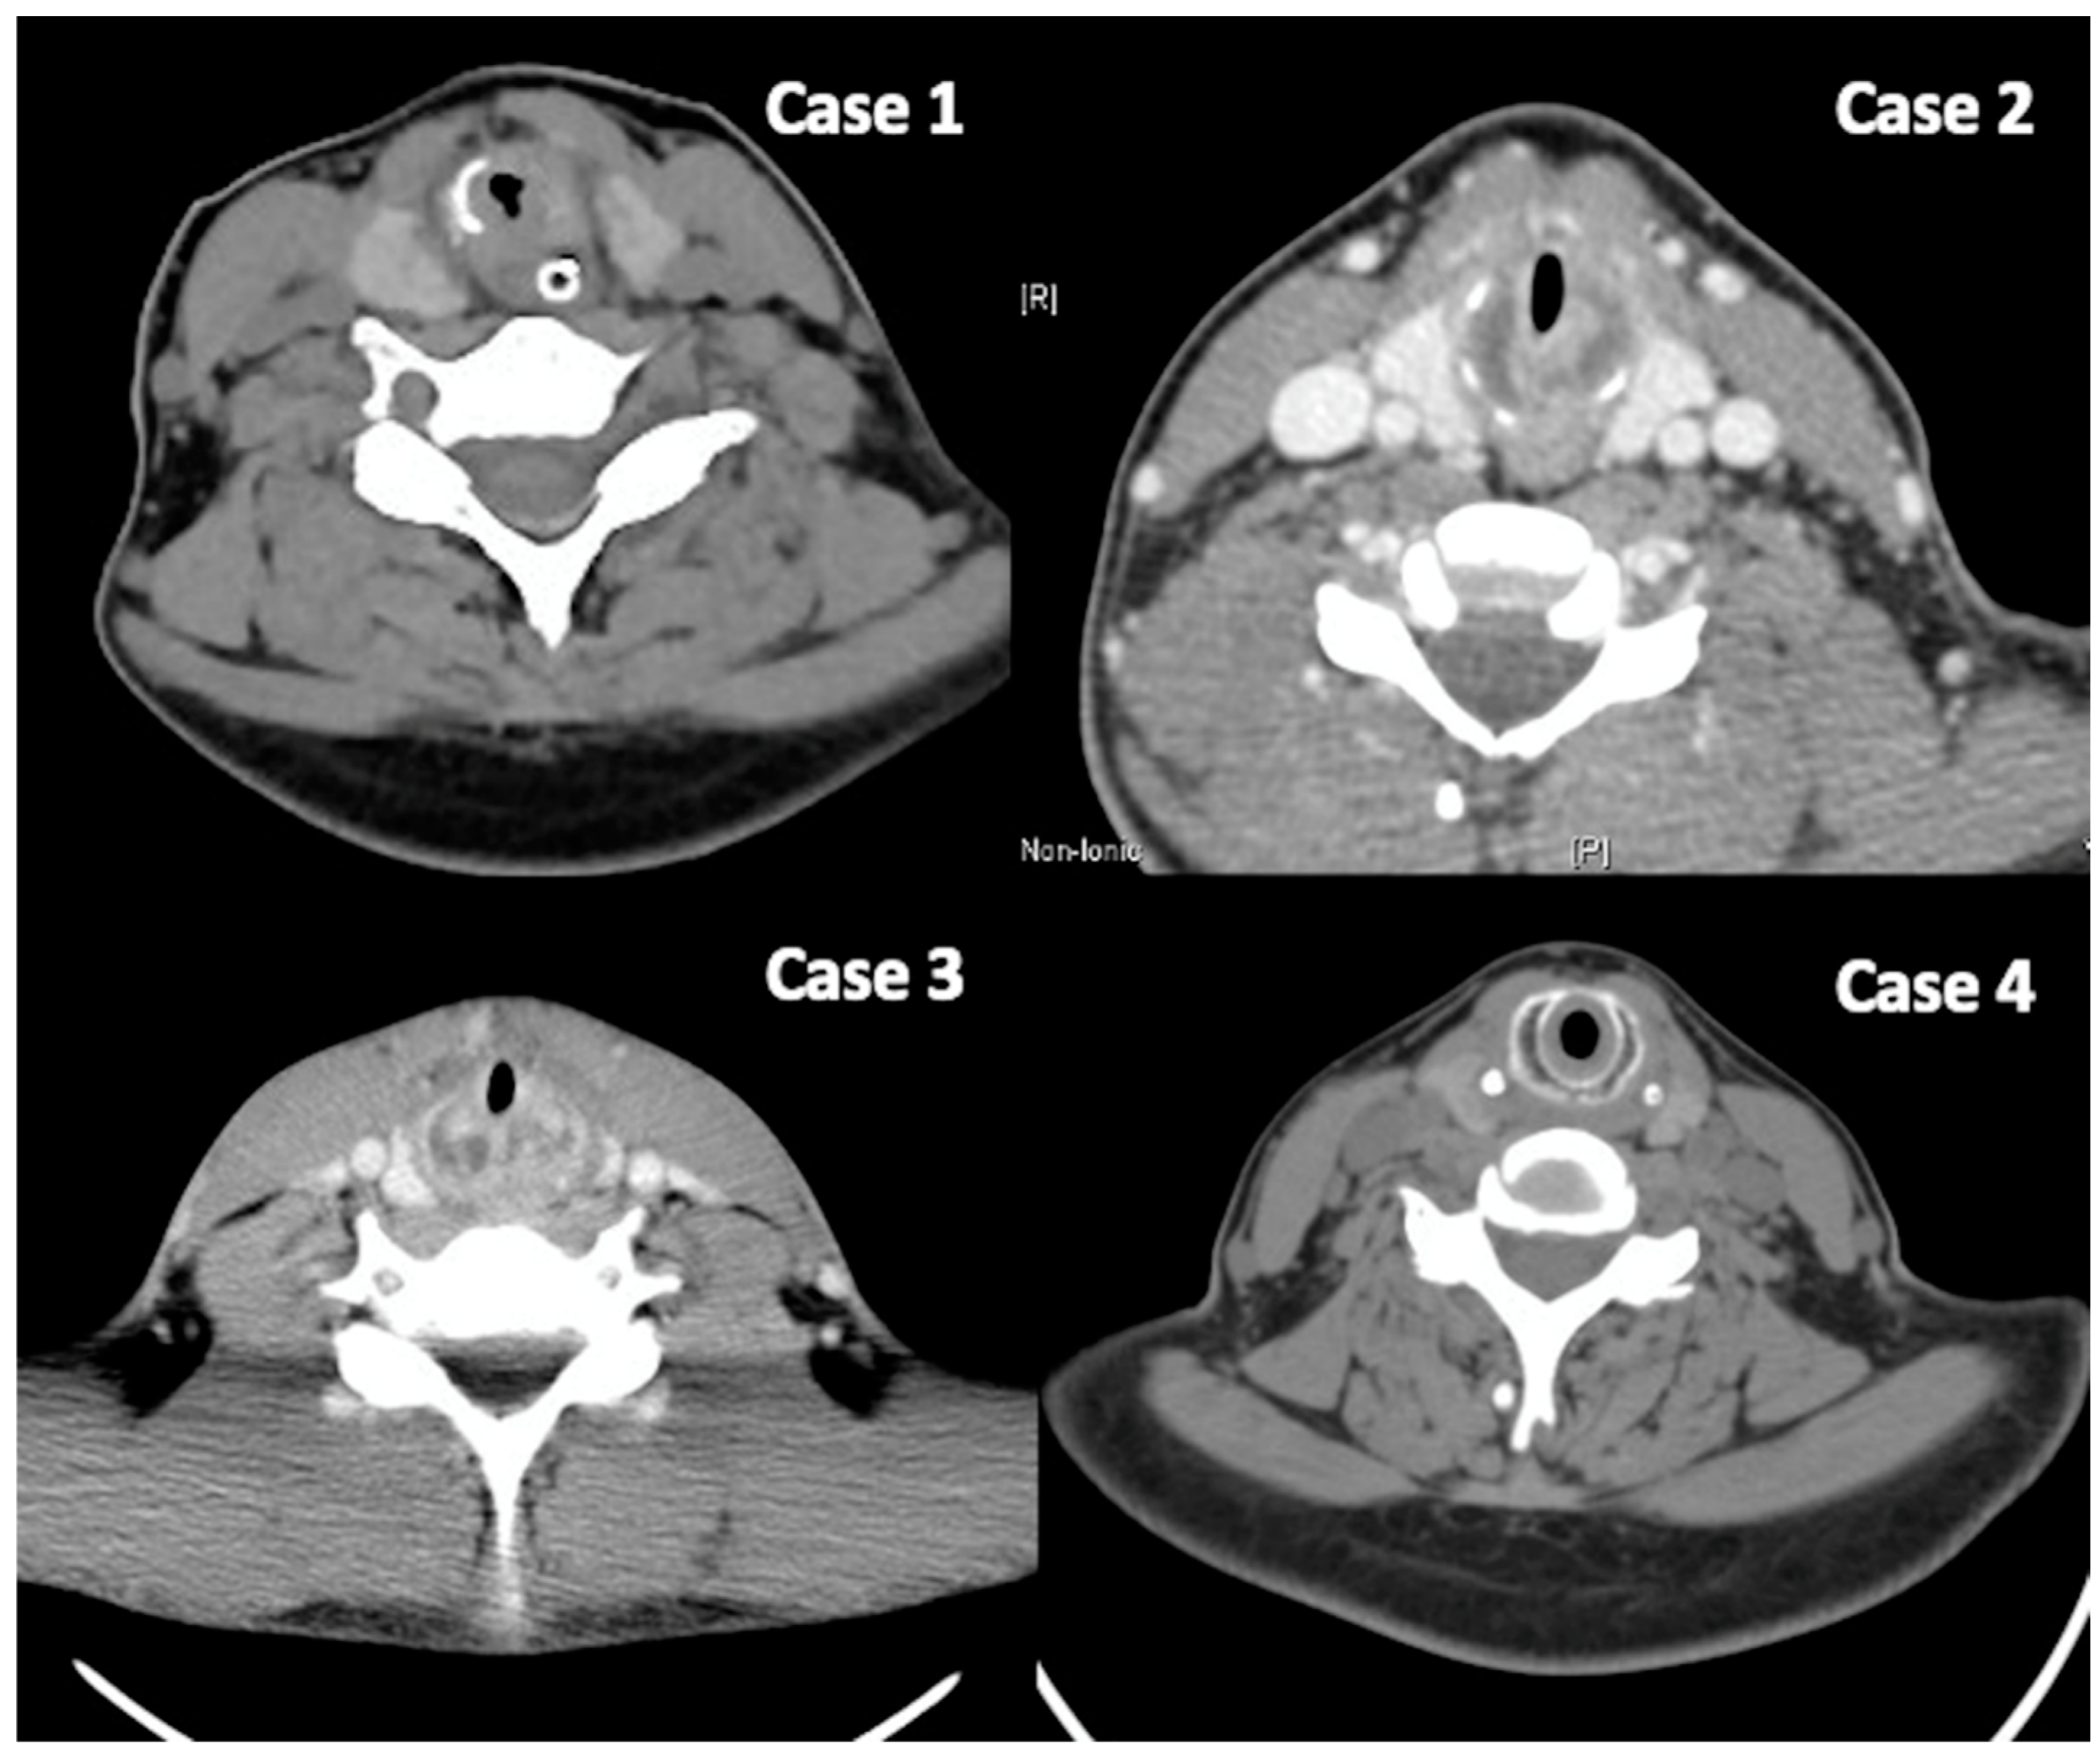

In the subglottic area, which is the only part of the respiratory tract comprising a complete ring of cartilage (cricoid cartilage), swelling or narrowing often causes relatively severe respiratory distress and may necessitate tracheostomy to maintain airway patency. In cases of RP with subglottic involvement, CT images can reveal thickening and edema of the subglottic mucosa and even destruction and deformation of the cartilage itself, suggesting disease-induced damage (Figure 1). In the larynx, in addition to mucosal edema, there is also visible destruction and deformation of the arytenoid cartilage. Differentiating between airway involvement due to GPA and relapsing polychondritis can be particularly challenging. Research indicates that GPA-related stenoses are typically subglottic and circumferential, and tend to occur in the subglottic region, whereas stenoses associated with relapsing polychondritis are more likely to be tracheal, anterior, calcified, and often extend to the bronchi, as seen on chest CT [17].

Figure 1. CT images revealed a thickened and edematous subglottic mucosa, along with destruction and deformation of the cartilage, indicating disease-induced damage.